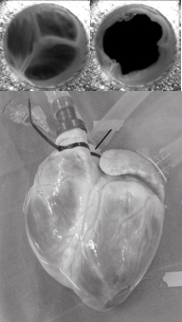

In einem gesunden Herzen sorgen komplexe dreidimensionale Strömungsmuster für einen effizienten Vorwärtsfluss des Blutes mit geringen Verlusten und verwirbelnden Strömungsmustern. In transparenten Modellen von Herzgeometrien können diese Strömungsmuster untersucht und die Auswirkungen verschiedener Pathologien analysiert werden. Veränderungen in diesen Wirbelströmungsmustern können sogar als Prädiktoren für Herz-Kreislauf-Erkrankungen verwendet werden.

Die verwendete Schlüsseltechnologie ist die Particle Image Velocimetry (PIV), mit der die Auswirkungen von linksventrikulären Unterstützungsgeräten analysiert werden, einschließlich Variationen der Unterstützung, verschiedener Positionen, kontrollierter Geschwindigkeitsmodi und patientenspezifischer Herzgeometrien. In Kombination mit der M3dRES-Infrastruktur werden mögliche Zusammenhänge mit Krankheiten (z.B. Thrombusbildung, Schlaganfall) untersucht.